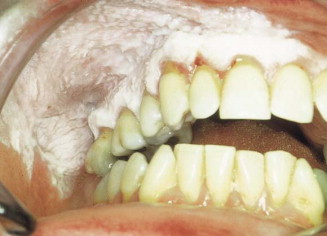

PRE-OP CLINICALLY

LEUKOPLAKIA